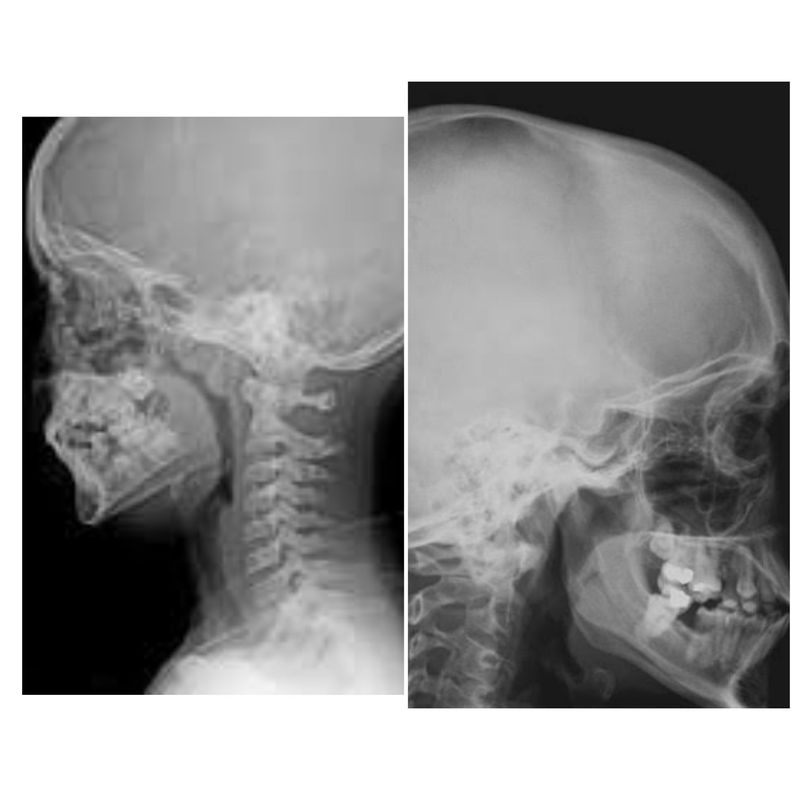

Compare the two x-ray films which show the lateral views of the paediatric skull. The air appears black and hence, the patent airway is black and any growth in the airway will obstruct it. The image on the left shows that the black of the nasopharynx is decreased due to a soft tissue growth just inferior to the skull base. This is the enlarged adenoid. Adenoids are masses of lymphoid tissues and are frequently enlarged in children, especially those who have upper respiratory infections. Compare it with the normally patent airway on the right where there is nothing obstructing the nasopharynx. Image via: www.radiopaedia.org